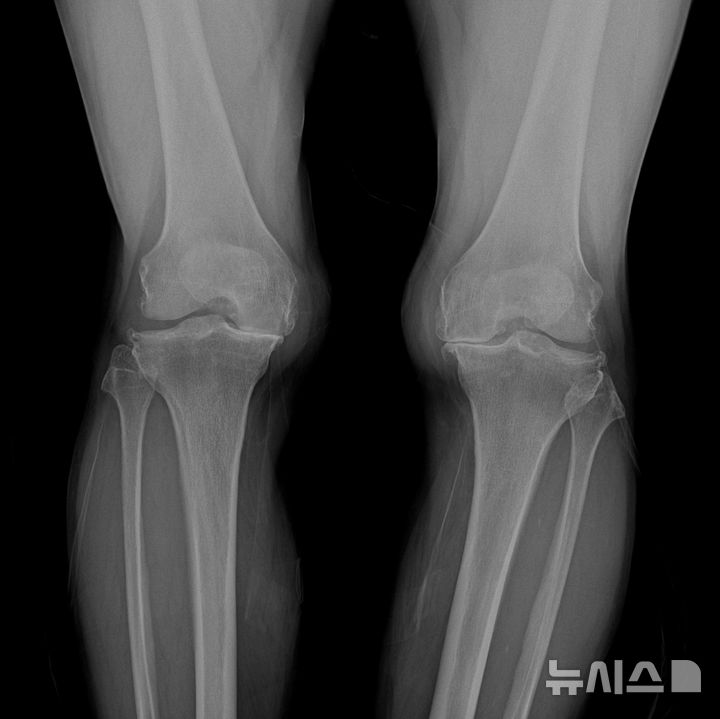

[서울=뉴시스] 퇴행성관절염 말기지만 인공관절 수술을 꺼리는 환자에게 냉각고주파 열치료술은 좋은 대안이 될 수 있다. (사진= 연세사랑병원 제공)

보건복지부 고시에 따르면 이 기술의 공식 명칭은 '무릎 골관절염 환자에서 냉각 고주파 열치료술'이다. 사용 목적은 무릎 통증 경감이며 ▲방사선학적으로 확인된 골관절염 2~4단계 환자 가운데 ▲진단적 신경차단술에서 통증이 50% 이상 줄어드는 반응을 보이고, ▲6개월 이상 약물치료를 포함한 보존적 치료에도 호전이 없는 경우에 시술할 수 있다.